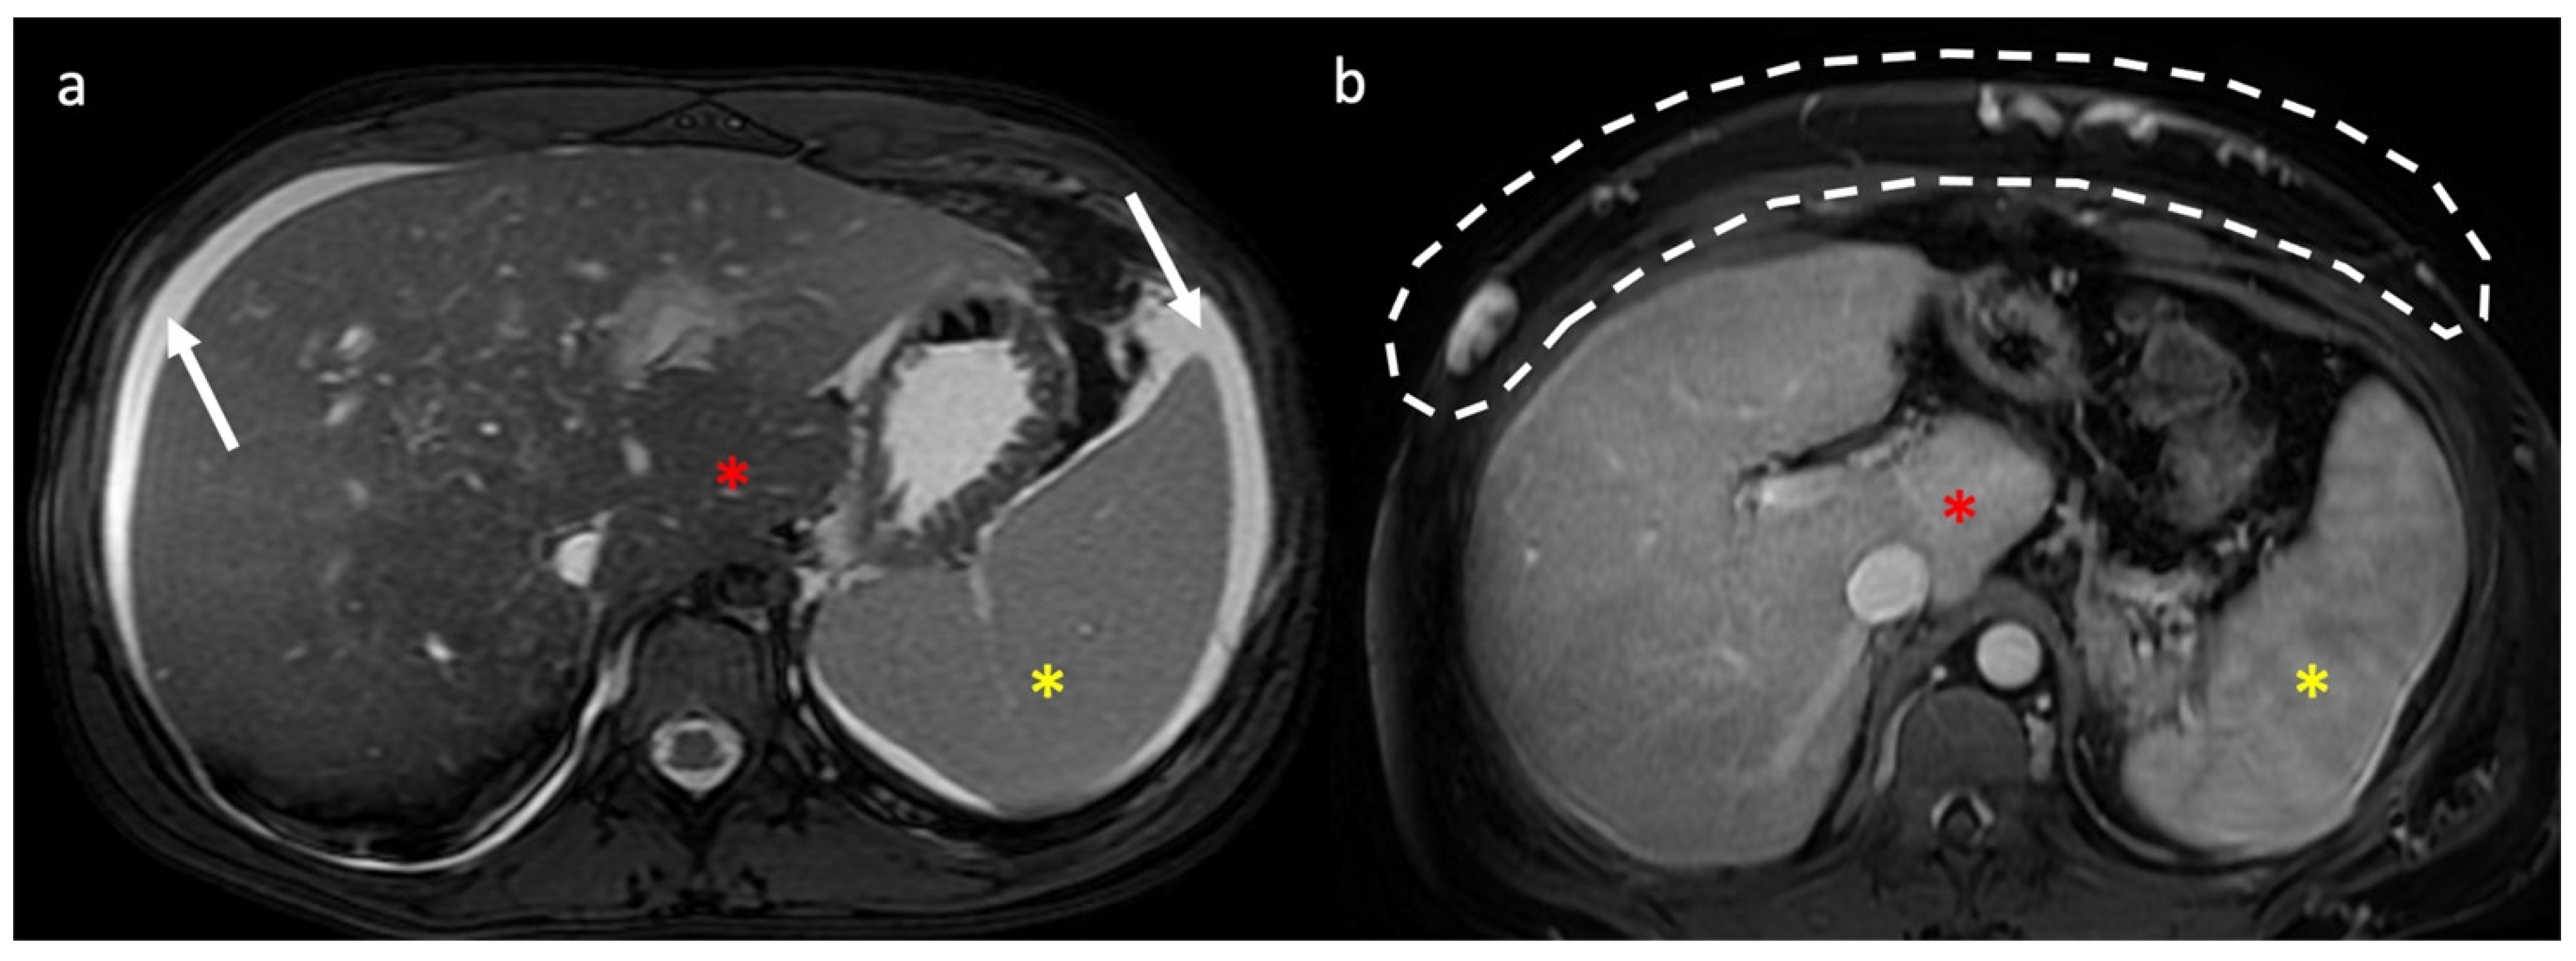

- Indirect signs: non-specific. They represent the consequences of long-standing hepatic venous impairment, including liver parenchymal changes with fibrosis and atrophy of involved segments and hypertrophy of unaffected territories (e.g., caudate lobe hypertrophy). On CT and MRI, centrilobular or sinusoidal congestion, represented as heterogeneous ”mosaic” enhancement after contrast media is also characteristic. Other signs include ascites, portal hypertension, and the presence of benign regenerative nodules, as well as hepatocellular carcinoma [6].

3.2. Computed Tomography and Magnetic Resonance: What to Look For

4. Hepatic Nodules

| MRI | Characterization of nodules (FNH-like nodules vs. HCC) T1-w decreased signal in hypoperfused regions, corresponding to high T2-w SI T2*-w flow void corresponding to thrombus. Hypointensity along the occluded vessels |